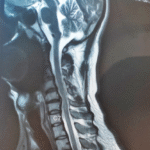

INVESTIGATION:

• MRI taken.

• Posterior disc bulge at the C5-C6 level, causing left neural compression.

7. MRI confirms disc bulge with corresponding nerve root compression